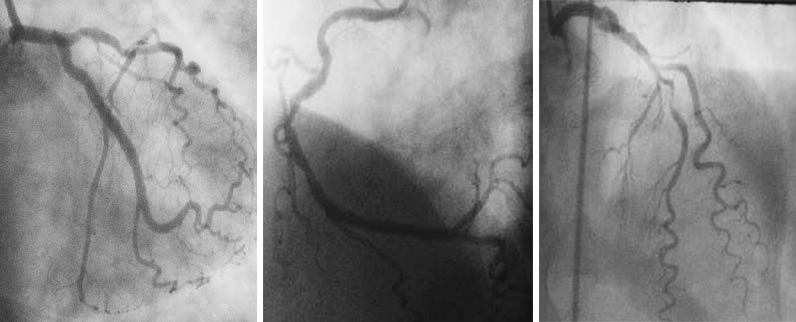

位于李树培院15楼的心导管及介入治疗中心(CCIC)添置了不少高科技仪器如数码平板血管造影系统、血管内腔超声波系统及最新3D光学相干断层扫描,为病人提供心脏介入检查,以了解心血管状况,协助医生作出准确诊断和适当治疗。

高科技仪器 本中心添置最新、最先进的仪器,全面配合优质的诊断及治疗服务: